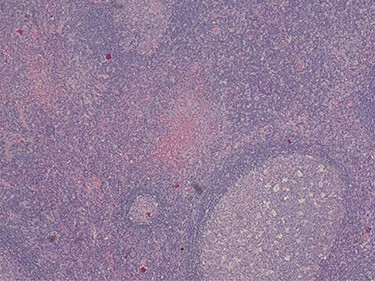

Because of the recent increase in the size of the swelling, the patient presented to our clinic and agreed to undergo excision of the swelling. A well-circumscribed swelling measuring 2.5 cm × 1.5 cm which was soft to firm in consistency was completely excised (Fig. 1). Histopathological examination showed sections of lymph node with florid follicular and germinal center hyperplasia (Fig. 2), and paracortical expansion by plasma cells, small lymphocytes and mast cells (Fig. 3). Marked eosinophilic infiltration with focal micro-abscess formation was present (Fig. 4). The features were consistent with Kimura’s disease. There was no evidence of malignancy. At 6 months follow-up, the patient had no evidence of recurrence.

Histopathology of the lymph node showing follicular and germinal center hyperplasia. Haematoxylin and Eosin stain. Magnification ×1.2.